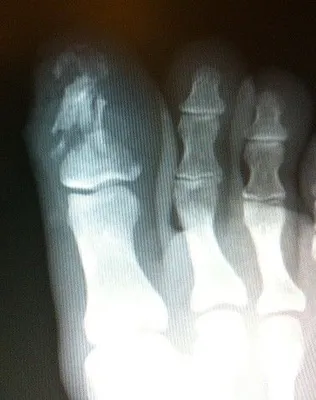

Below is an x-ray image of an extra-articular fracture of the proximal phalanx of the hallux (great toe) of a child. the fracture line does not enter the joint.